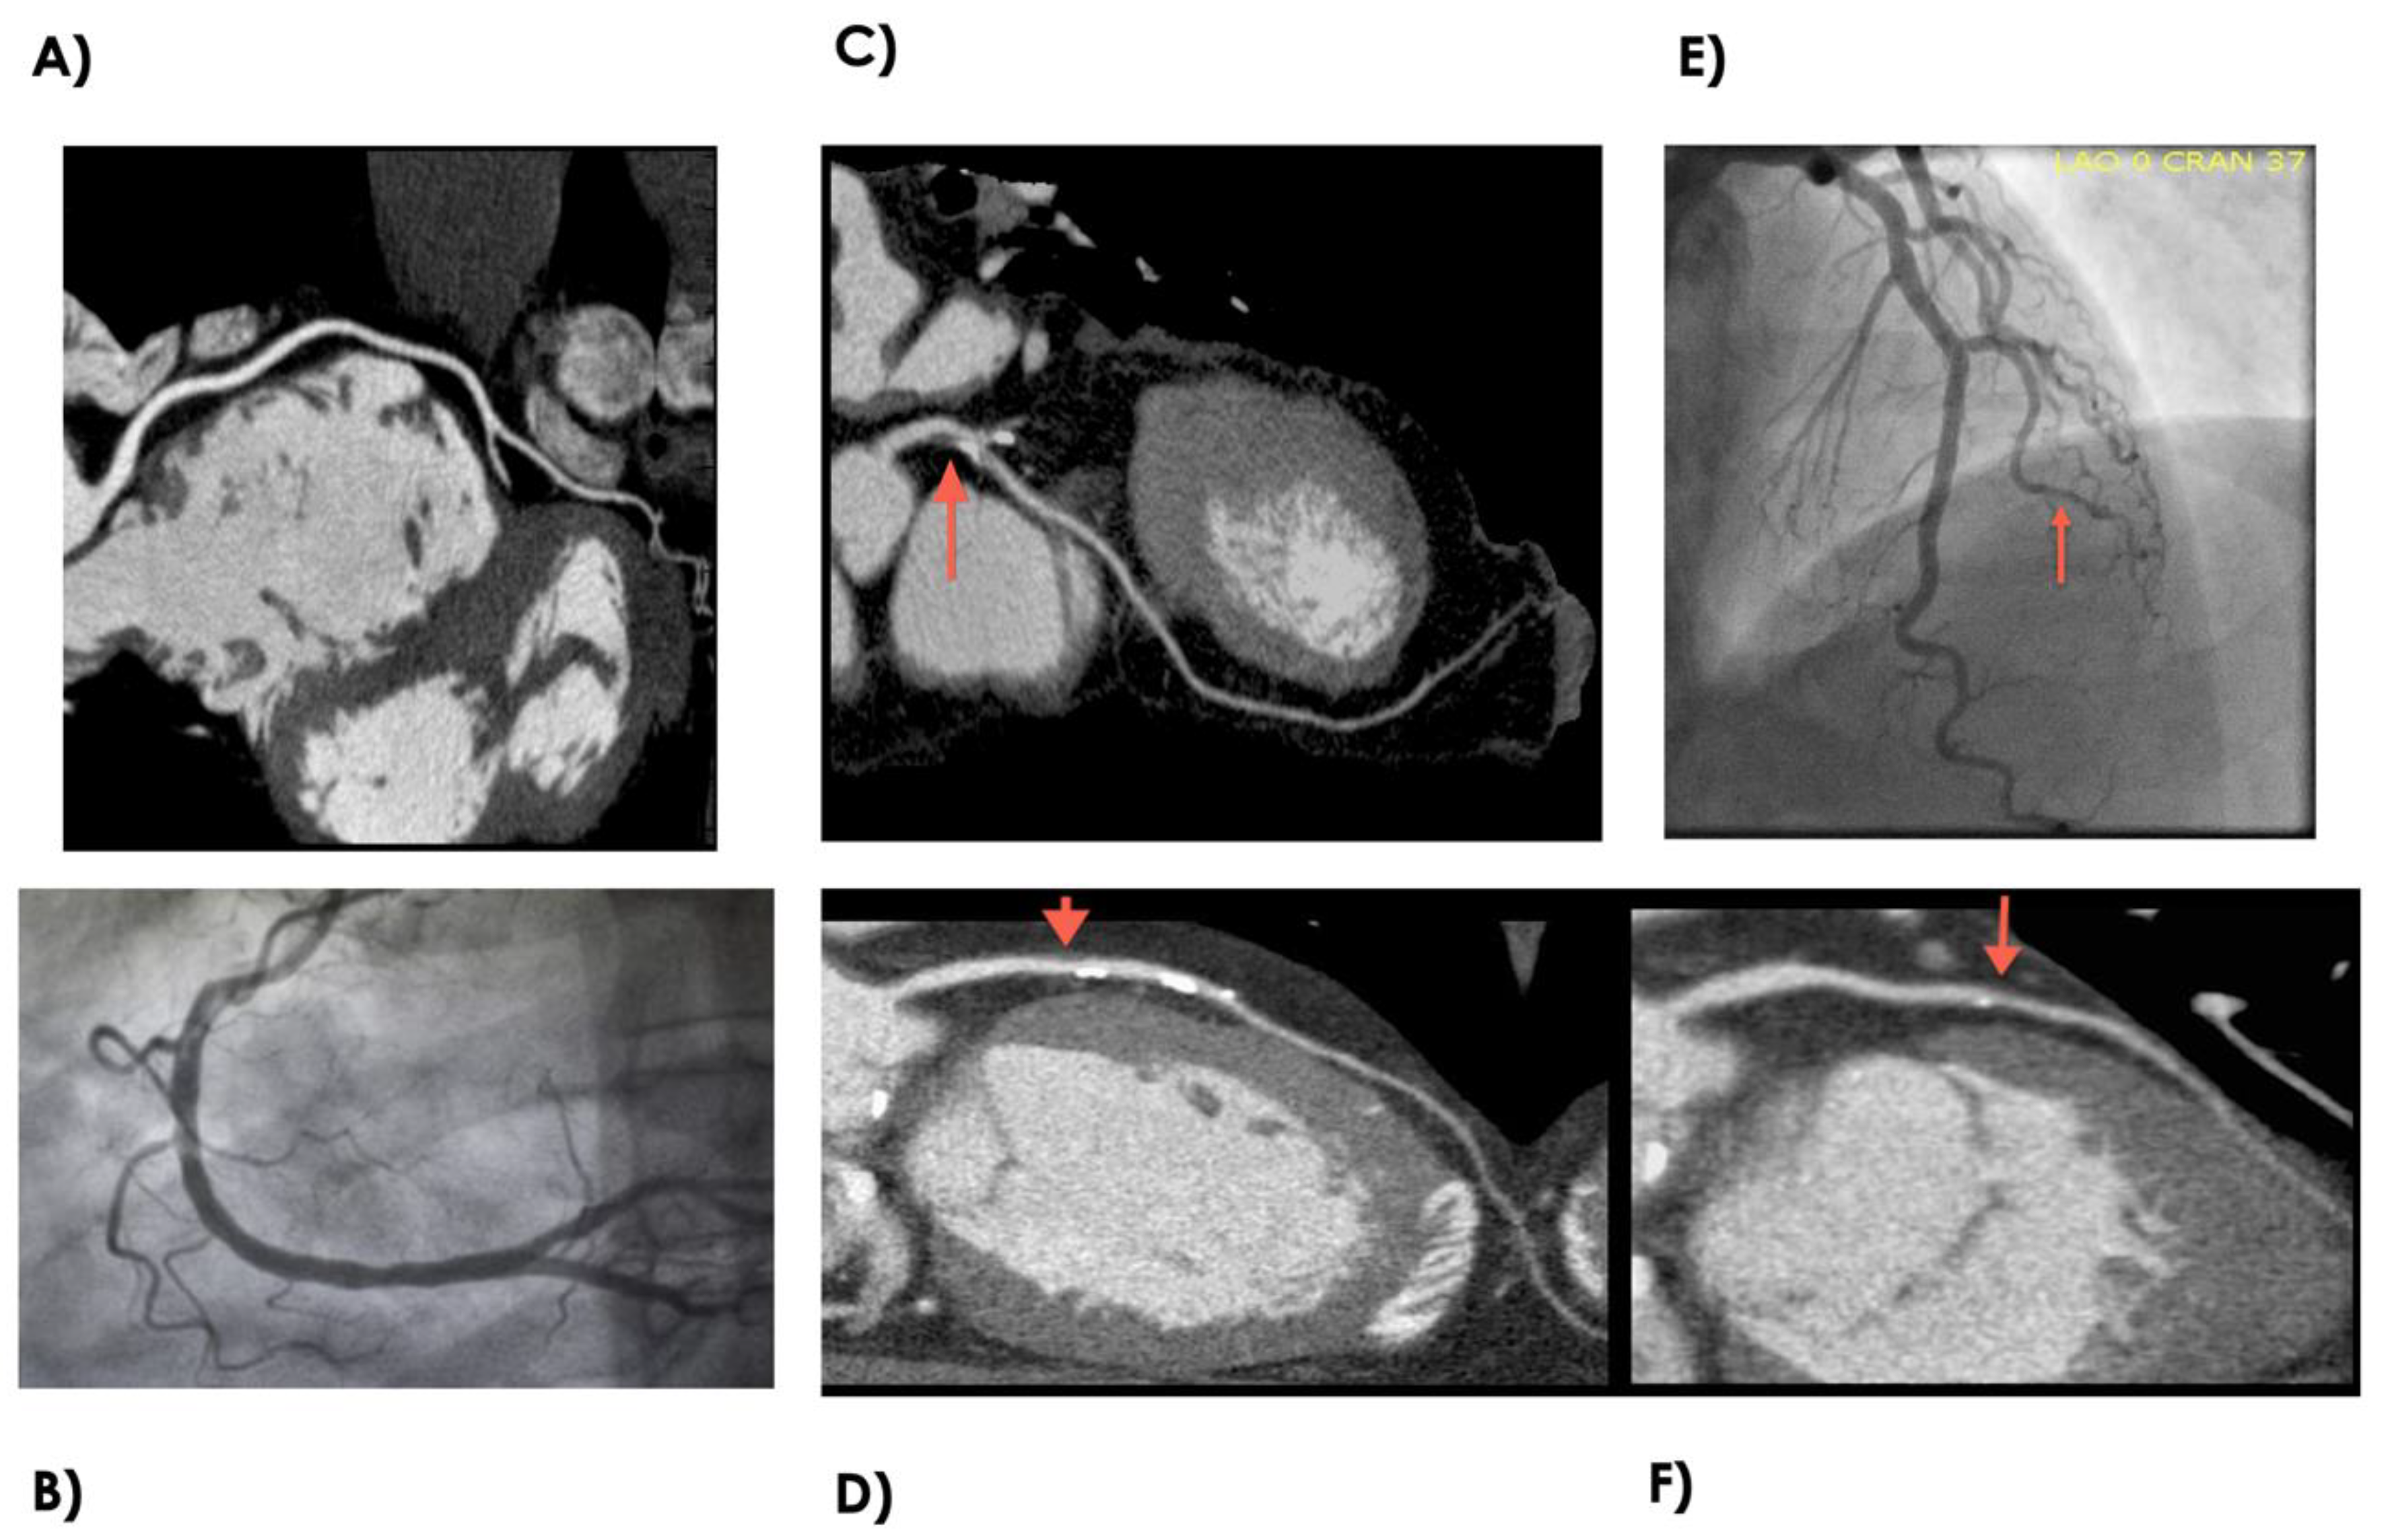

Medicina Free Full Text Severe Coronary Artery Disease In A Person Living With Hiv Html

Combined Assessment Of Subtended Myocardial Volume And Myocardial Blood Flow For Diagnosis Of Obstructive Coronary Artery Disease Using Cardiac Computed Tomography A Feasibility Study Journal Of Cardiology